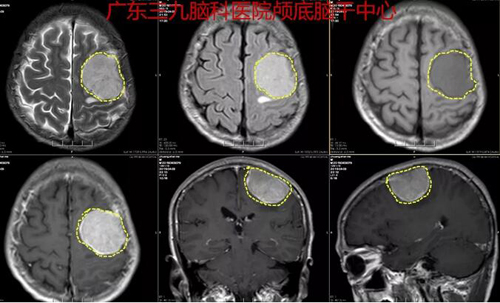

图2:术前MR示1.左侧顶部脑膜瘤并侵犯邻近颅骨,病变大小约为4.95cm×4.28cm×3.14cm,增强后,病变呈较均匀明显强化,并可见脑膜尾征;邻近脑组织受压移位并可见片状长T1长T2水肿信号影,FLAIR序列呈高信号;2.脑MRV检查提示右侧横窦、乙状窦变细,考虑发育因素